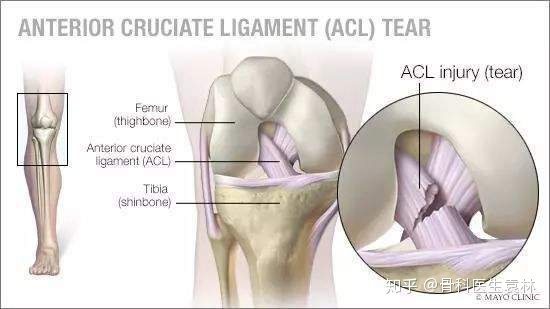

前十字韧带

膝关节十字韧带又称交叉韧带,位于股骨内外髁之间,前后两条,互相交叉。前十字韧带,位于膝关节内,连接股骨与胫骨(起于股骨髁间窝外后部,向前、内、下止于胫骨棘前侧),主要作用是限制胫骨向前过度移位。后十字韧带

前十字韧带损伤

膝关节过伸或过度外翻可引起膝关节前十字韧带损伤。如为过度外翻引起,可同时发生内侧付韧带断裂。前十字韧带损伤合并内侧半月板损伤也较常见。后十字韧带损伤